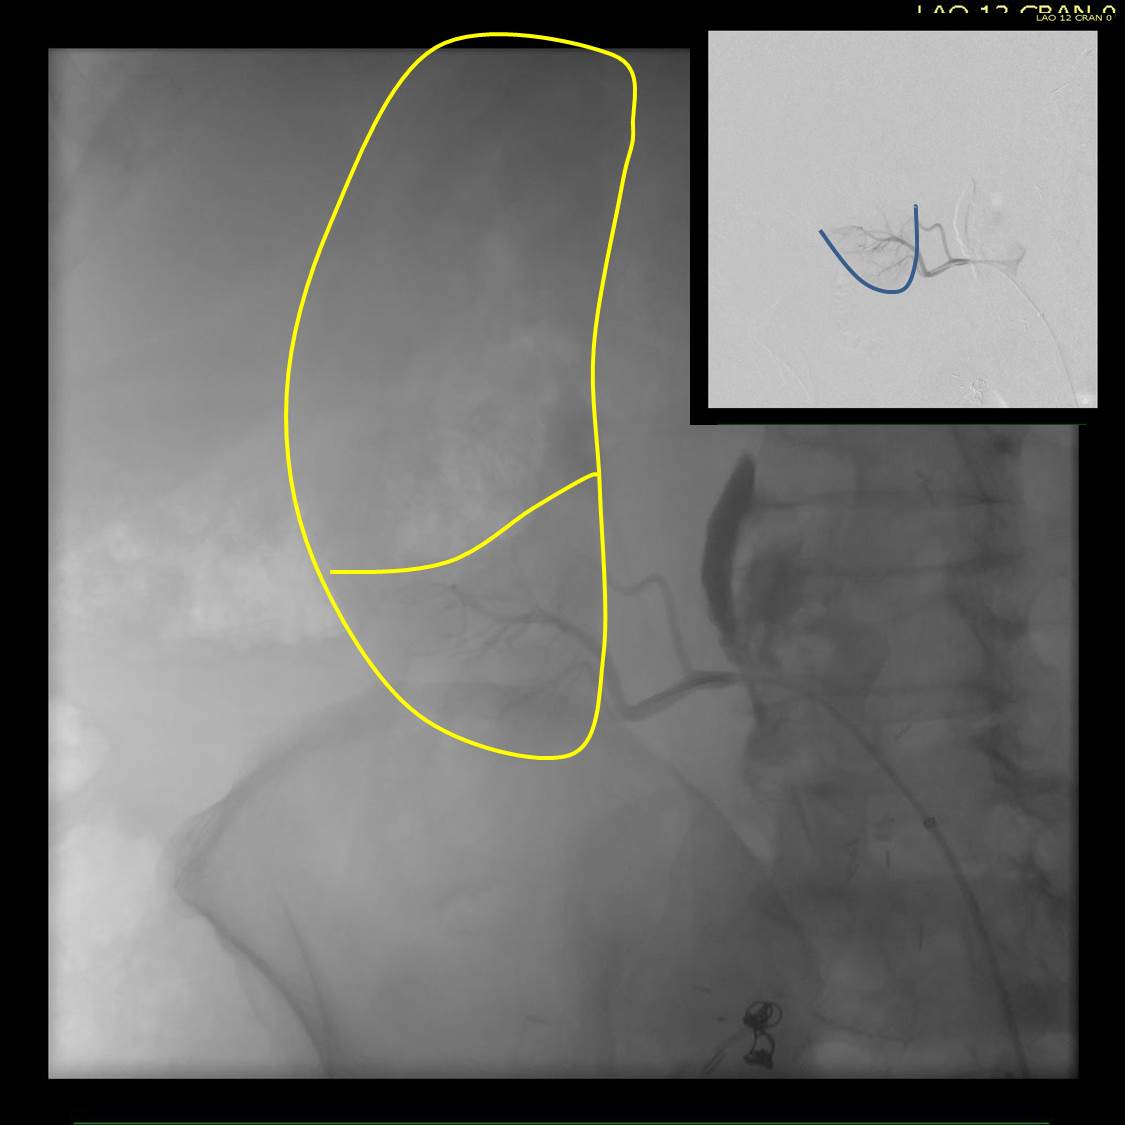

Type Ib Endoleak Causing re-Rupture of a previous r-AAA after no surveillance

Take this patient who had previously ruptured his AAA and undergone EVAR. Several years out from his rupture, he ruptured again from a type Ib endoleak due to aneurysmal degeneration of his right common iliac artery. Per his family, he never followed up. Perhaps he assumed he was cured of his disease? Repairing this was tricky, primarily because I hopped up and down, thinking, “I could cure this!” An open revision with a bifurcated graft would eliminate the need for EVAR surveillance, avoid abdominal compartment syndrome, and the physiologic consequences of a large retroperitoneal hematoma. But who wants a laparotomy? Not this patient, who was hypovolemic shock, and whose family chose the minimally invasive option that everyone assumes is better.

Not a clamp

I took him to the hybrid operating room, balloon occluding to stabilize his blood pressure, embolizing the normal internal iliac artery and extending the stent graft into the external iliac artery.

Completion -there is an Amplatzer plug in the right internal iliac artery

This patient stabilized and had abdominal tightness due to his large hematoma which did not need evacuation. After a stay lengthened by concern for abdominal compartment syndrome, moderate pain, fevers, and bilirubinemia (due to the hematoma), he was discharged and never showed up for followup. None of the phone numbers work. Without followup, EVAR is a menace. We will keep trying.